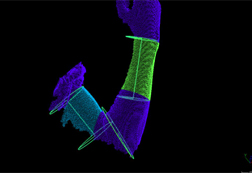

特集 ハンディ3Dスキャナーをリハビリで利用する

2. 手の”むくみ”を診断する。むくみ・ある/なしの状態を1ミリ精度で表現する。

|

|

|